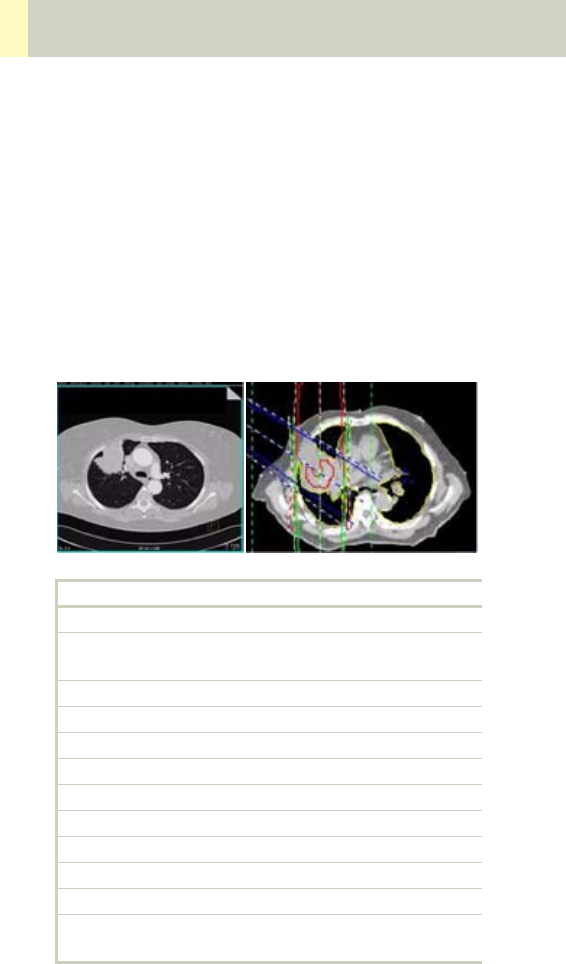

Non-square Matrix for 3D Recon

If you perfrom a 3D reconstruction of your spiral scan

you have the possibility to choose between three dif-

ferent FoV matrices: 512 square, 512 non-square, 256

non-square. In some cases it is already saved to the

scan protocol (Spine, CarotidAngio) set up a new scan

protocol or want to modify an existing one you can

save the non-square matrix together with the recon

parameters.

• 512 square: the FoV stays quadratic with a 512x512

matrix size.

• 512 non-square: the FoV can be adjusted as a rectan-

gle to your needs, for example spine reconstruction.

Its max. side ratio is 1:4.

• 256 non-square: the FoV can be adjusted as a rectan-

gle to your needs but with a lower matrix size and a

lower resolution for example RunOff , Cardiac recon-

structions. The maximum side ratio is then 1:8.

If you use the non-square matrix and you extend the

side length of your FoV more then the max. ratio then

the shorter side will be stretched to fit into the ratio

again.

You will find the FoV displayed in the image text for the

non-square matrix. It will be displayed like this: FoV X

x FoV Y.

Case Examples for 3D Recon and Non-

Square Matrix

Some scan protocols are delivered with predefined

oblique and non-square matrix reconstructions.

These protocols are marked with the suffix “VOL”

•Coronal and sagittal reconstruction of the spine: